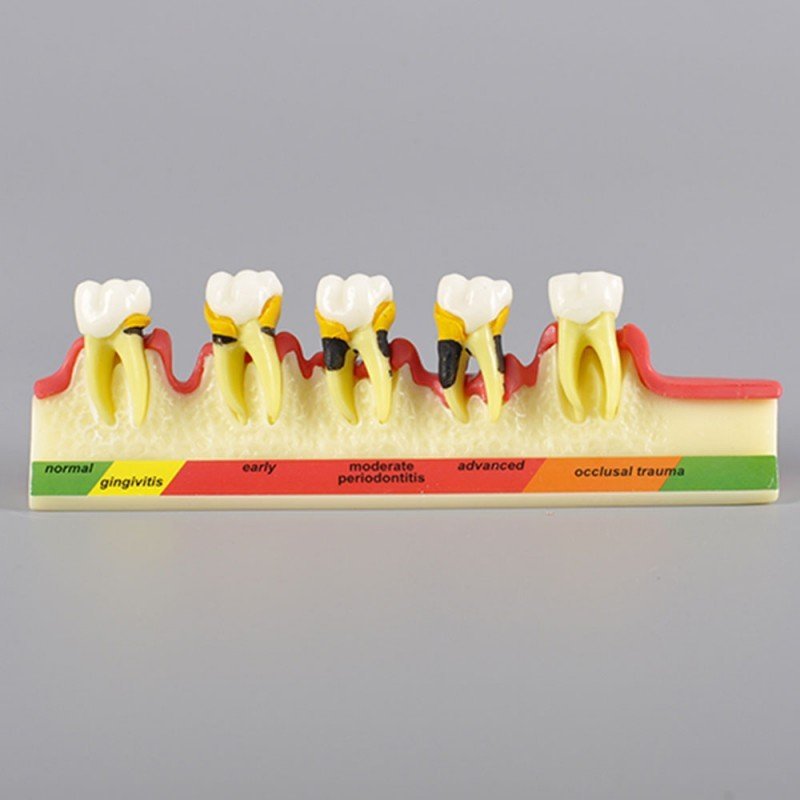

The Dental Periodontal Disease Model is a highly detailed, cross-sectional teaching tool that effectively illustrates the complete progression of gum diseaseÊ from healthy gingiva to advanced periodontitis and bone resorption. This model includes five molar teeth, each representing a specific stage in periodontal health, making it a powerful visual aid for dental professionals.

Crafted from durable resin, the model showcases healthy gums on the far left, followed by stages of gingivitis, early periodontitis, moderate periodontitis, and finally, severe periodontitis. It also features occlusal trauma, highlighting the impact of bite stress on periodontal health. This compact yet informative model is ideal for clinics, dental colleges, and chairside patient education.